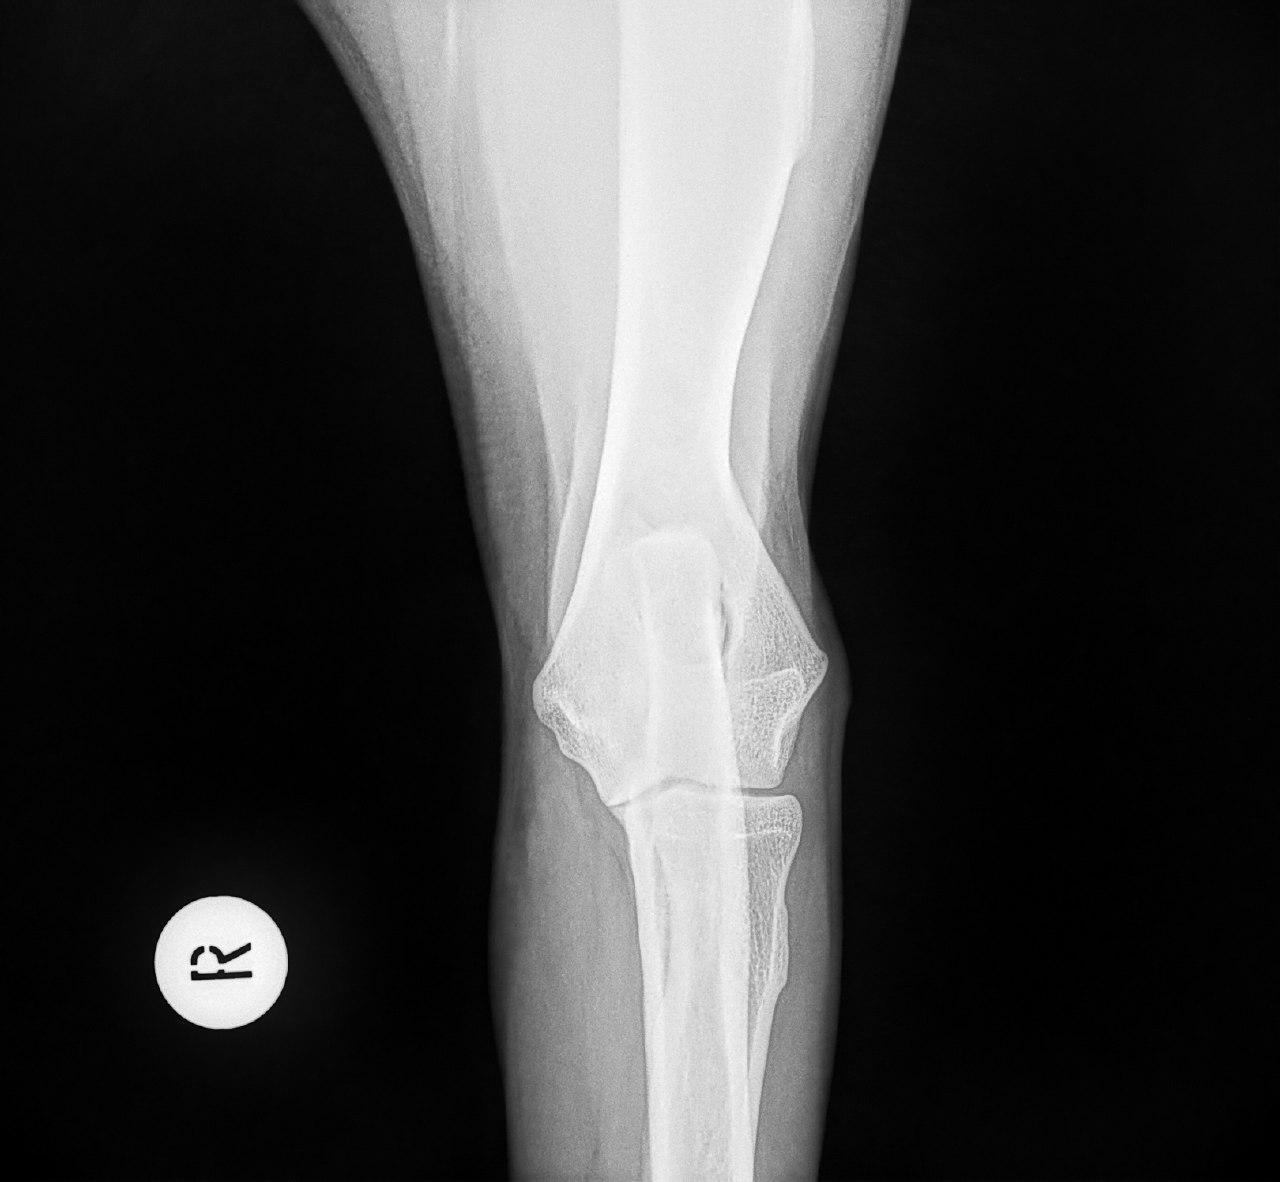

Mit der HD ist das so ne Sache..... die Vererbung spielt eine sehr große Rolle, ja. Aber bei unserer Peggy Zb ist es so, dass mehrere Generationen nachweislich HD und ED frei sind und auch frei von Spondylosen. Als einziger Hund überhaupt in der gesamten Zucht hat unsere Dame alles mitgenommen, was zu kriegen war;(: sie hat nicht nur schwere HD, weil ihre Hüfte viel zu locker ist, sondern dadurch bedingt am rechten Knie bereits schwere Arthrose und hinten links eine Sehenschwäche (durch Überlastung), weshalb sie dort durchtrittig ist. Und als würde das alles nicht schon vollkommen reichen, wurden aktuell auch noch mehrere heftige Spondylosen diagnostiziert;(. An einer Stelle ist sogar schon etwas abgebrochen8|.